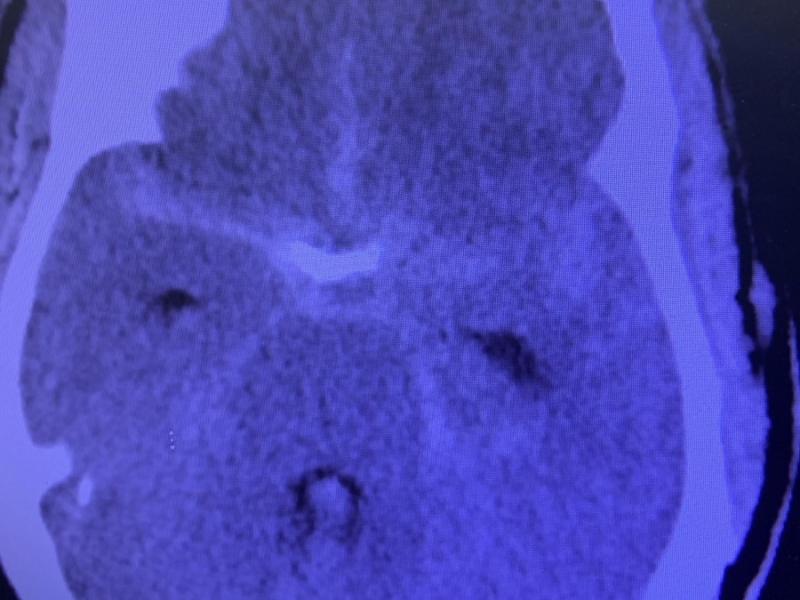

Non-traumatic Subarachnoid Hemorrhage Treatment Maintain